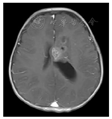

CT检查:左侧脑室体部团块状稍高密度影(图1),CT值约38 HU,大小约32.6 mm(前后径)×28.3 mm(左右径)×29.1 mm(上下径),左侧脑室后角明显扩大。MRI平扫+增强:(1)左侧脑室体部团块状混杂信号,T1WI、T2WI以等高信号为主,其内可见小片状低信号,FLAIR呈等高信号,DWI以高信号为主,增强扫描后肿块中心可见不均匀中等强化,余颅内未见明显异常强化(图2,图3,图4,图5);(2)MRS:肿块内测量NAA/Cr降低,Cho/Cr、Cho/NAA明显升高(图6);(3)头颅MRA未见明显异常;脑电图示轻度异常脑电图。影像检查提示高级别恶性肿瘤性病变,首先考虑间变性室管膜瘤,脉络丛乳头状癌及胚胎性肿瘤不除外。

GG在颅内的影像表现具有多样性,是一种少见的颅内原发性肿瘤,好发于大脑半球的浅表部位,多见于颞叶。影像上主要分为囊性、囊实性、实性3种。囊变和钙化被认为是节细胞胶质瘤的常见表现。Majores等[10]认为囊性病变并壁结节钙化是GG的特征性表现之一。本例发生于左侧脑室前角内,较为罕见,病变以软组织密度/信号为主,内见散在斑片状钙化,没有脑室外GG常见的囊变表现。病变局部与左侧脑室前角壁分界欠清,磁共振DWI呈较高信号,提示弥散受限,多考虑高级别肿瘤;结合MRS示NAA/Cr降低,Cho/Cr明显升高,术前影像首先考虑间变性室管膜瘤,其次考虑脉络丛乳头状癌。幕上室管膜瘤/间变性室管膜瘤分属WHO Ⅱ~Ⅲ级,幕上可位于侧脑室、脑实质或骑跨生长[11],肿瘤内可出现钙化、囊变和出血,密度或信号较为混杂,DWI提示弥散受限时,多考虑间变性室管膜瘤。本例未见明显囊变和出血成分,增强后未呈现室管膜瘤典型的环形强化[12],与室管膜瘤/间变性室管膜瘤不太符合。脉络丛乳头状瘤好发于脑室,尤其是侧脑室内,WHO分Ⅰ~Ⅲ级,Ⅲ级脉络丛乳头状癌具有高级别恶性肿瘤特征性表现:DWI弥散受限、合并出血、钙化、囊变,可突破侧脑室壁侵犯邻近脑实质,也可随脑脊液播散转移[13],因常起源于脉络丛,可分泌脑脊液,示侧脑室扩大,与本例较为相似。不过结合冠状位观察本例病变部分阻塞侧脑室侧孔可能是导致左侧脑室积水主要原因;因肿瘤生长挤压侧脑室壁变形扩大且分界不清,而并非直接侵犯侧脑室壁。此表现影像鉴别尤为重要,本例肿瘤DWI呈现较高信号,提示弥散受限,且MRS提示Cho/Cr明显升高,易与侧脑室好发恶性肿瘤混淆。术后回顾分析图像本例以实性为主伴少量钙化,不伴水肿及周围组织侵犯,发生于孟氏孔附近,符合节细胞胶质瘤良性表现,但考虑到弥散受限以及MRS中Cho/Cr明显升高,笔者认为不除外肿瘤向更高级别演变可能,这需结合临床长期随访,总结经验。